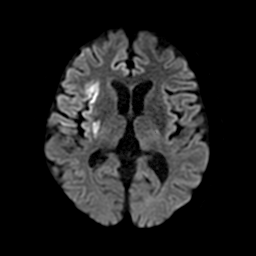

2-1. 低吸収領域の検出・表示例(下)

頭部CT検査において、周囲に比べ白く映る部分(高吸収領域)が見られる場合には、脳出血が疑われます。脳出血は高血圧・脳腫瘍・脳血管の異常などが要因となり、脳の動脈が破れて脳内部に出血した状態を指します。一方、周囲に比べ黒く映る部分(低吸収領域)が見られる場合には、脳梗塞が疑われます。脳梗塞は、脳内の血管が詰まるなどにより血液の流入が止まり、脳に酸素や栄養が行き渡らなくなる状態です。また、急性期の脳梗塞では、頭部CT検査において、灰白質と白質の境界が消失するなどの所見(ECS=early CT sign)が見られ(2)、こうした所見を見落とさずに治療につなげることが肝要です。